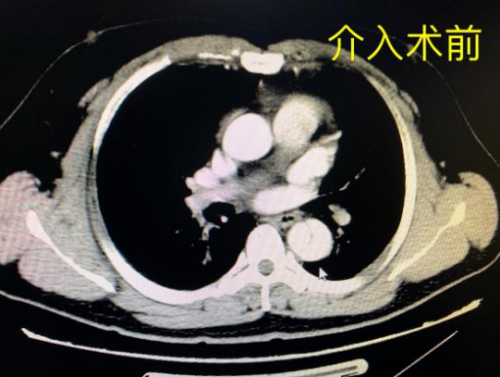

“患者因无明显诱因突发胸背部撕裂样剧烈疼痛,不能缓解紧急入院,在急诊科予以紧急处置。”据立博体育|实时赛事直播与比分|权威专家分析与体育竞猜平台 急诊科主治医师黄钰财介绍,经检查,患者血压急剧升高达242/142mmHg(正常90-135/60-90mmHg)、脉搏105次/分,胸腹部增强CT提示:主动脉夹层(Stanford B型),经过胸外科、外周血管介入科急会诊,因病情危重转入急诊ICU严密监护,予以止痛、镇静、降压,同时完善术前检查与准备。

术前CT影像学检查示主动脉“撕裂”为三层